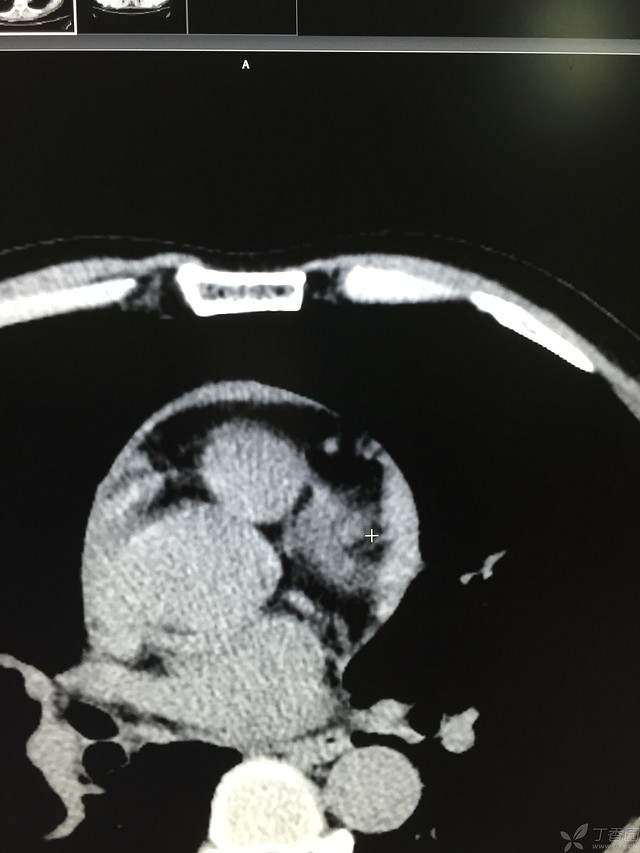

胸痛三天,加重三小时(CT是心包高密度影是什么)

患者性别:男

患者年龄:64岁

简要病史:三天前休息时突发胸前区疼痛伴大汗,到当地医院输液治疗后缓解,3小时前情绪激动后再次出现胸痛伴大汗,胸部压迫感,持续不缓解入院,到当地医院测血压180/?mmHg泵入硝酸甘油转入我院。

体格检查:血压94/72mmHg(右侧)96/74mmHg(左侧),心率78此/分,其他未见阳性体征